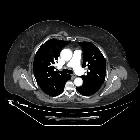

CT

- appears as a flat parasternal muscle, longitudinal in orientation